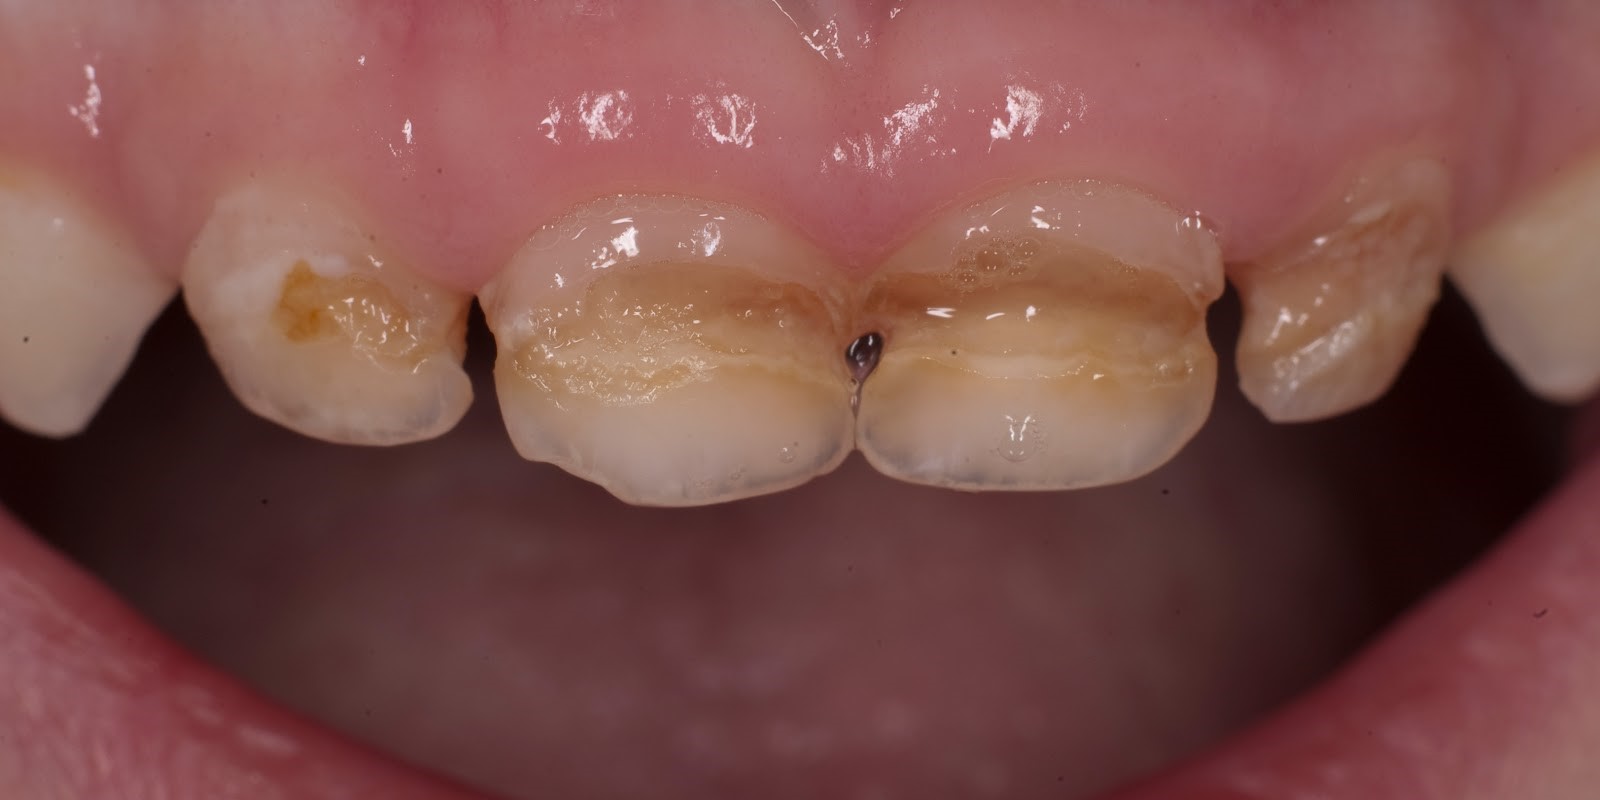

На фотографии изображен кариес в пришеечной части зубов.

Распространение кариеса чаще всего происходит между зубами, в фиссурах (бороздки и канавки) зубов, в пришеечной части зубов. Для того чтобы его обнаружить стоматологи используют различные методы обследования.

- Визуальный осмотр производиться с помощью специального зеркала. При осмотре проблемного зуба может быть обнаружено характерное пятно коричневого, бежевого или серого цвета. Также выявляется кариозная полость различной глубины. В детском возрасте локализация кариозных полостей происходит на жевательной поверхности постоянных или временных моляров.